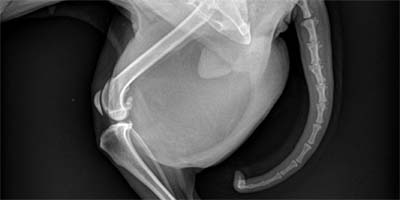

Presentation:This is an 8 year old female Chihuahua with a large, firm thigh area.